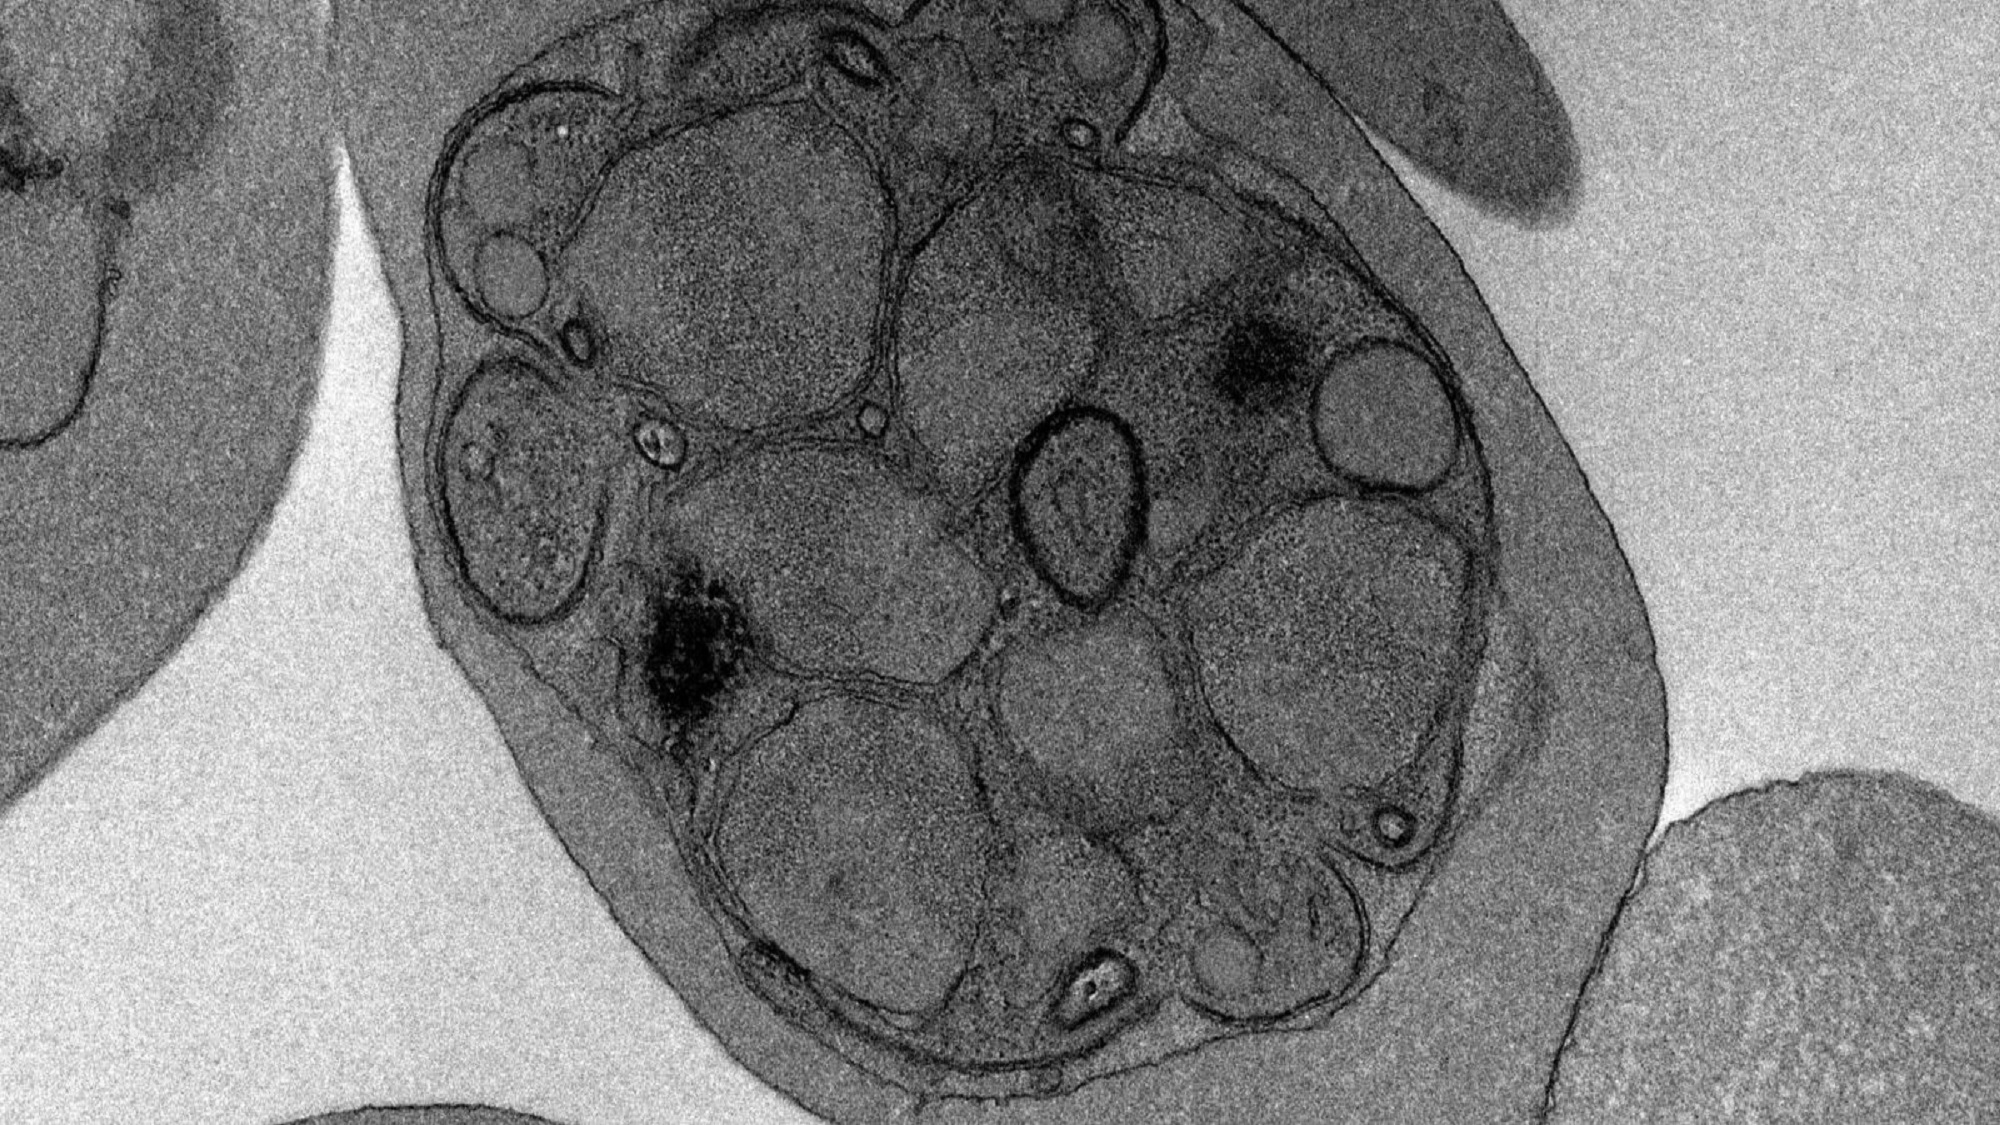

This image of the week, taken with an electronmicroscope, shows the ultrastructure of PfGNA1-disrupted Plasmodium falciparum. Taken by Maria Pia Alberione, a PhD student at the Barcelona Institute for Global Health (ISGlobal), the image is part of a recent study that has found a potential new and safe way to attack the malaria parasites by targeting one of their key metabolic steps.

But the ISGlobal team, led by Luis Izquierdo, found a weak point in a metabolic pathway the parasite relies on to anchor critical proteins to its surface and help maintain its structure. In particular, they saw that the PfGNA1 enzyme, which is essential for this pathway, is structurally very different from its equivalent in humans. And when they disrupted the PfGNA1 gene in the parasite, they saw a dramatic loss of these anchor proteins, which led to an arrest of the parasite development, preventing their escape from red blood cells and effectively blocking further invasion.

These results hint to PfGNA1 as a potential target for future drugs that could affect the parasite, without attacking the human proteins.